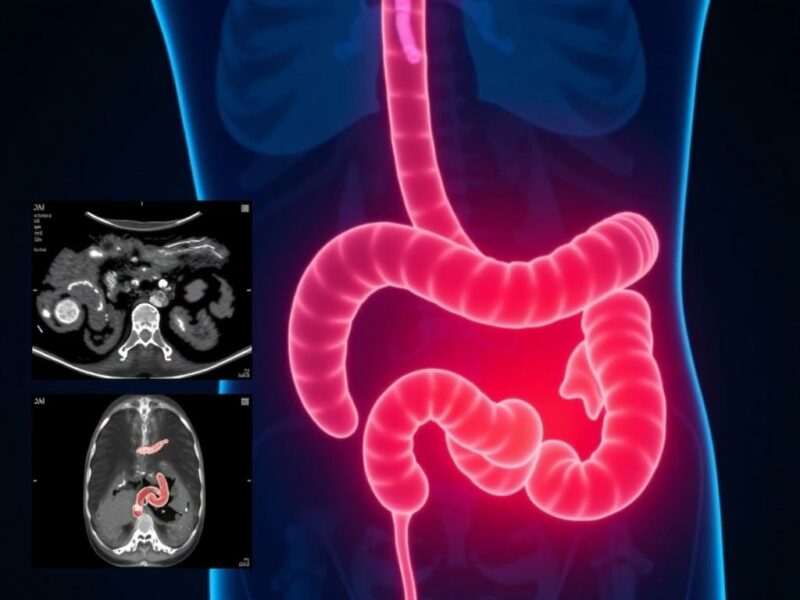

Imagenología: ecografía, TC y RM — cómo elegir y cuándo

La ecografía abdominal dirigida por un operador experimentado es la primera elección en muchos centros pediátricos por su seguridad (sin radiación) y su disponibilidad. Sin embargo, su rendimiento depende en gran medida de la experiencia del ecografista, del estado del niño (inquietud, dolor) y de factores anatómicos como la obesidad o la posición del apéndice. Un informe de ecografía “no concluyente” es frecuente y plantea la necesidad de decisiones clínicas complementarias.

La TC abdominal es la prueba con mayor sensibilidad y especificidad para apendicitis, pero su uso en niños está limitado por el riesgo de exposición a radiación ionizante, que tiene implicaciones a largo plazo. Muchas instituciones usan protocolos de baja dosis o reservan la TC para casos con ecografía no concluyente y sospecha persistente. La resonancia magnética (RM) evita radiación y ofrece excelente resolución, pero no siempre está disponible de forma urgente y requiere que el niño permanezca quieto; la sedación es a veces necesaria.

La elección entre estas pruebas debe basarse en la probabilidad clínica, la disponibilidad local, la edad y el estado del paciente. En centros con ecografistas pediátricos experimentados, la ecografía es una herramienta muy valiosa que, junto con la vigilancia clínica, evita muchas TC innecesarias.